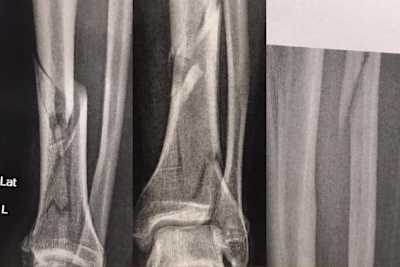

Doch sein Teamkollege Patryk Kosiniak, Sieger des Yamaha R6 Dunlop Cup 2016, kam im Freien Training von Assen gerade mal eine Runde weit. Sturz auf einer noch nicht ganz trockenen Stelle, Krankenhaus, Operation. Diagnose: Doppelter Unterschenkel-Bruch links. Die Saison dürfte damit gelaufen sein. Am Samstag-Abend erwischte es Sarah Heide vom Team Suzuki Laux. Zwar auf zwei Rädern, aber ohne Motor. Die IDM Superbike-Pilotin war mit dem Fahrrad unterwegs und stürzte unglücklich. Diagnose: rausgesprungene Kniescheibe. Zumindest die Rennen in Assen sind für Heide gestrichen. Damit fehlt eine der zwei Damen im Feld und es ist an Kawasaki-Pilotin Lucy Glöckner, die bei ihrem IDM-Comeback auf dem Schleizer Dreieck flott in die Top Ten gerauscht war, die Ehre der weiblichen IDM-Abteilung zu retten. Aus auch für Jessica Langstädtler vom Yamaha R6 Dunlop Cup. Sie verletzte sich bei einem Sturz im Training an der Schulter und übte sich anschliessend übers Strecken-Mikrofon als Co-Kommentatorin.